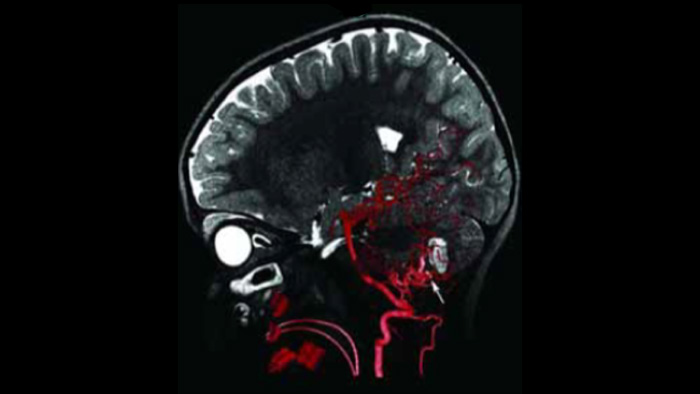

O Roteiro de RM-TC oferece a possibilidade de sobrepor uma varredura do SmartCT Angio ou de RM por angiografia adquirida anteriormente com fluoroscopia ao vivo para visualizar os limites da lesão e a vascularização correspondente para avaliação de risco. A reutilização de dados pré-adquiridos ajuda a gerenciar a dose de raios X e o meio de contraste.